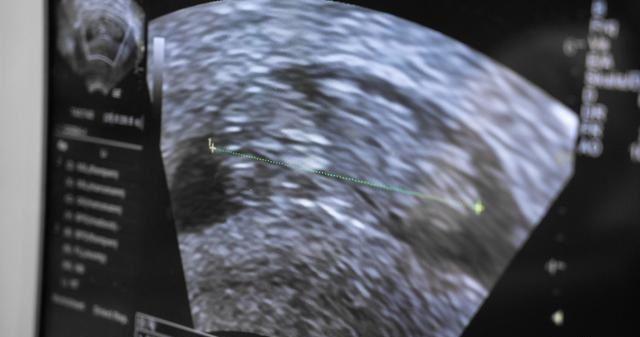

做b超有哪些常见问题呢?B超可以直接显现出胎儿的发育过程,还可以帮助有妇科疾病的人确认是否有囊肿或是包块。在妊娠的中期还可以看出胎儿是否会出现畸变等异常。那么做b超是从下面做吗?孕期做b超检查子宫有囊肿有关系吗?

b超检查不是从下面做的,需要进行b超检查的器官大多集中在腹部,如肝脏、胆囊、女性的子宫以及卵巢等。

其原理是通过专业的设备向待检查器官发出超声波,声波返回的情况会在经过专业处理后在显示器上成像,医护人员可以根据该成像判断患者的患病情况。

对于孕期妇女来说,B超检查也可以比较直观的检测到其腹中胎儿的发育是否良好。